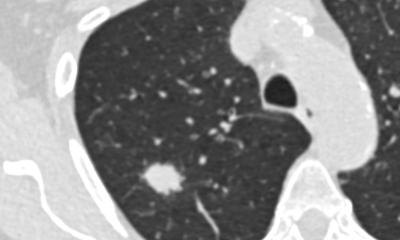

Bildquelle: Lange123, Thorax CT pcor Cut 3D Volume Rendering Haut, CC BY-SA 3.0

Ein geeignetes Verfahren für die Früherkennung von Lungenkrebs könnte die Low-Dose-CT sein. Eine CT ist eine Röntgenuntersuchung, bei der man liegend durch ein ringförmiges Gerät geschoben wird. Dabei rotiert eine Röntgenquelle um die ausgewählte Körperregion und misst aus unterschiedlichen Richtungen deren Dichte. Ein Computer setzt die so gesammelten Daten später zusammen, es entsteht ein mehrdimensionales Schnittbild der betreffenden Körperregion. Eine CT-Aufnahme ist mit einer Strahlenbelastung verbunden. Bei der Low-Dose-CT wird durch die Veränderung verschiedener CT-Parameter wie Röhrenspannung und -strom eine Reduzierung der Strahlendosis erreicht – bei ausreichender Bildqualität für die Befundung.